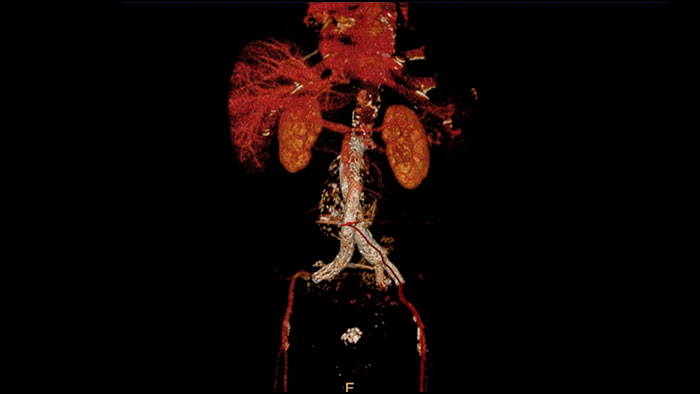

Advanced Vessel Analysis (AVA)

Multi Modality Advanced Vessel Analysis (AVA)

Comprehensive vascular analysis planning

Designed to examine and quantify different types of vascular lesions from CTA and MRA scans. It accommodates different modes of inspection, allows labeling different vascular lesions, and helps navigating through multiple findings.

Demonstrated to reduce the post-processing time by 50% when compared to manual Head & Neck CT angiography (CTA) analysis*.

Benefits

• Ability to choose which Head & Neck Bone Removal method to be used (Standard vs. Smooth).

• Customizable Volume rendering “smoothness” for the 3D Head & Neck vascular structure using a smoothness control.

* Ardley N et al. Efficacy of a new post processing workflow for CTA head and neck. ECR 2013 / C-1760.